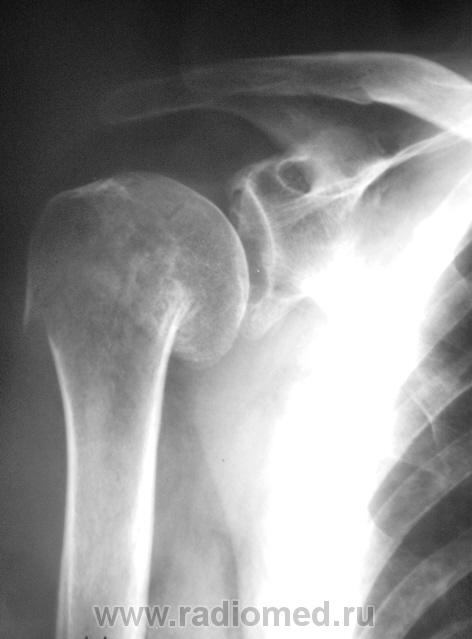

Случай № 1. Пациент направлен хирургом на рентгенографию плечевого сустава. 2 дня тому - травма.

Вколоченный перелом шейки плечевой кости с отрывом большого бугра. Варусная деформация на уровне перелома.

хирургической шейки плеча со смещением дистального отломка краниально.